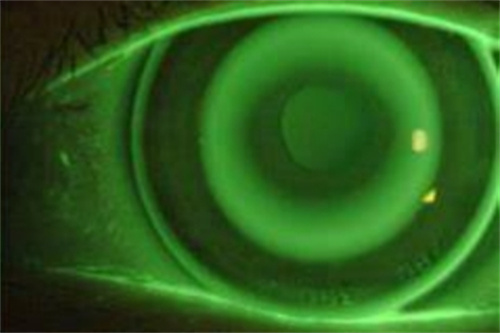

角塑镜片在使用过程中,会接触到泪液中的蛋白质。这些蛋白质在镜片表面逐渐沉积,形成一层薄膜。如不及时清除,这层薄膜会越来越厚,影响镜片的透光性和矫正治疗状态好。蛋白质沉淀还会成为细菌滋生的温床,增加眼部感染的风险。因此,定期除蛋白是保持镜片清洁和佩戴可靠的重要步骤。

除蛋白处理并不复杂,但需要按照正确的方法进行。首先,将镜片放入专用的除蛋白液中,浸泡一段时间。然后,用清水深度冲洗镜片,确保除蛋白液完全被清除。后,将镜片放入护理液中保存。需要注意的是,除蛋白液不能直接接触眼睛,否则会引起刺激。除蛋白处理的频率应根据个人使用情况来调整,一般建议每周进行一次。